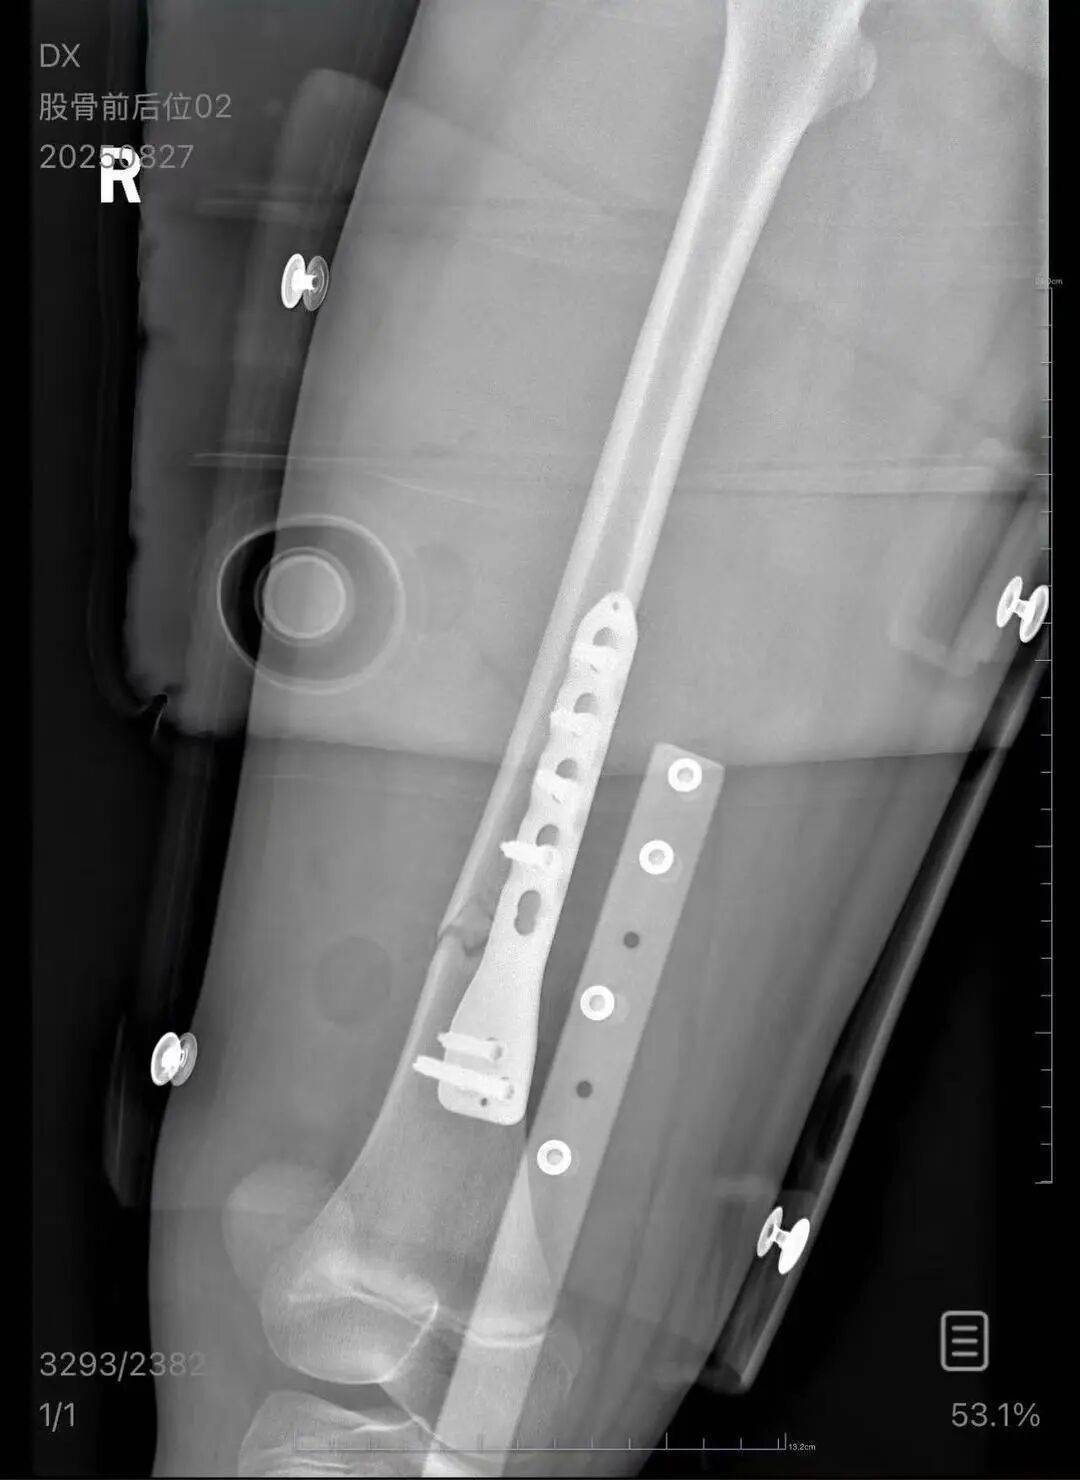

▲朱女士女儿手术后拍的X光片 受访者供图

朱女士向记者出示的医院病历显示,8月24日凌晨,朱女士的女儿到医院就诊越南抹茶交易所。医院诊断朱女士的女儿右股骨骨折,需要住院进一步治疗。